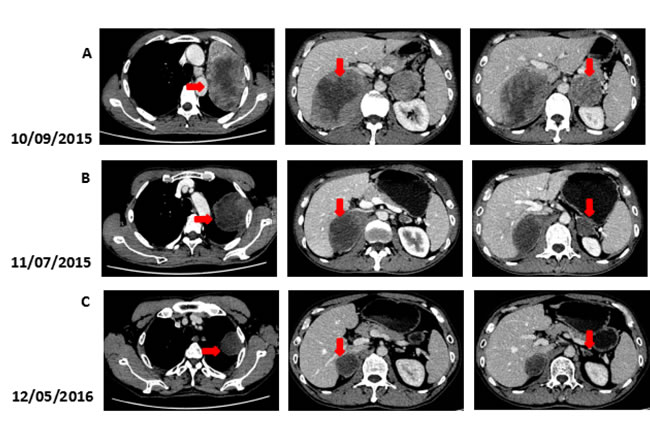

Figure 3: Computed tomography (CT) findings. (A) The CT scan shows the lesion in left lung and bilateral adrenal (arrows). (B, C) A restaging CT scan shows the lesion in left lung and bilateral adrenal keep shrinking after two, fifteen courses of Nivolumab (arrows).

We recommended immunotherapy with Nivolumab at a dose of 3 mg/kg, once every 2 weeks since October 10, 2015. The first three days after the administration, the patient had fever, and the maximal body temperature of 39.2oC. After symptomatic treatment of fever, patient’s body temperature returned to normal. The next day, the patient felt left anterior chest relaxation. A week later, the chronic back pain was significantly reduced, and overall physical fitness was improved although there was still a mild cough. Occasionally bloody sputum and dyspnea symptoms disappeared completely. The results of the two periodic imaging showed that the left lung and bilateral adrenal lesions were dramatically decreased. The evaluation of response rate is partial remission (PR) based on Recist1.1 standard. Subsequently, the patient continues to receive 5 cycles, 10 cycles, 15 cycles and 24 cycles of immunotherapy with Nivolumab. Because of the good effect, the patient uses Nivolumab every 3 weeks since the 21th cycles. The imaging results indicated that the lesion was continuously to shrink (Figure 3, Figure 6). The number of T cell subsets of patient’s peripheral blood increased to normal after the above-mentioned therapy (Figure 4). Only neuron specific enolase (NSE) is abnormal among all tumor markers in this patient, but it was decreased to normal range after the following treatment (Figure 5). The progress-free survival (PFS) time of this patient has not been reached.